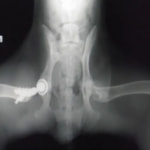

重度股関節形成不全の症例

THR法を実施した症例のレントゲン写真